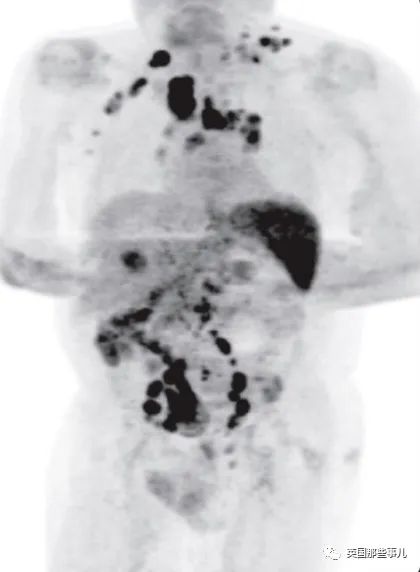

他患有霍奇金淋巴瘤,已到晚期,CT检查显示他体内到处都有活跃的癌细胞…

黑色部分为癌细胞